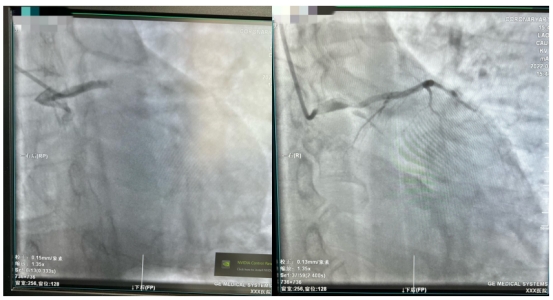

在从江北患者家中送往医院的路上,急救医生就将心电图发到ac米兰官网中文网站一院胸痛中心微信群里,医生会诊后即启动导管室做好手术准备。到医院后,在无核酸结果的情况下,张先生直接被推进急诊负一层的负压导管室,而此时张先生已有心率减慢、血压下降状况。经紧急冠脉造影后发现,冠状动脉左主干尾部被一个大血栓阻塞,远端完全闭塞。在非常凶险情况下,医师立即为他植入IABP(主动脉内球囊反搏装置)以维持血压,并在IABP保护下行冠脉内血栓抽吸和支架植入术,几分钟后张先生的血管被开通,命总算被救了回来。患者入医院大门到导丝通过病变时间仅为30分钟,而从急救医生接触患者到导丝通过病变时间也仅为50余分钟。

到达医院后,刘先生在无核酸报告的情况下被推到负压导管室,紧急造影显示为左主干尾部90%狭窄,前降支近端90%狭窄并血栓影,回旋支完全闭塞。刘先生在IABP保护下成功进行了左主干血管开通,入医院大门到导丝通过病变时间仅为29分钟。